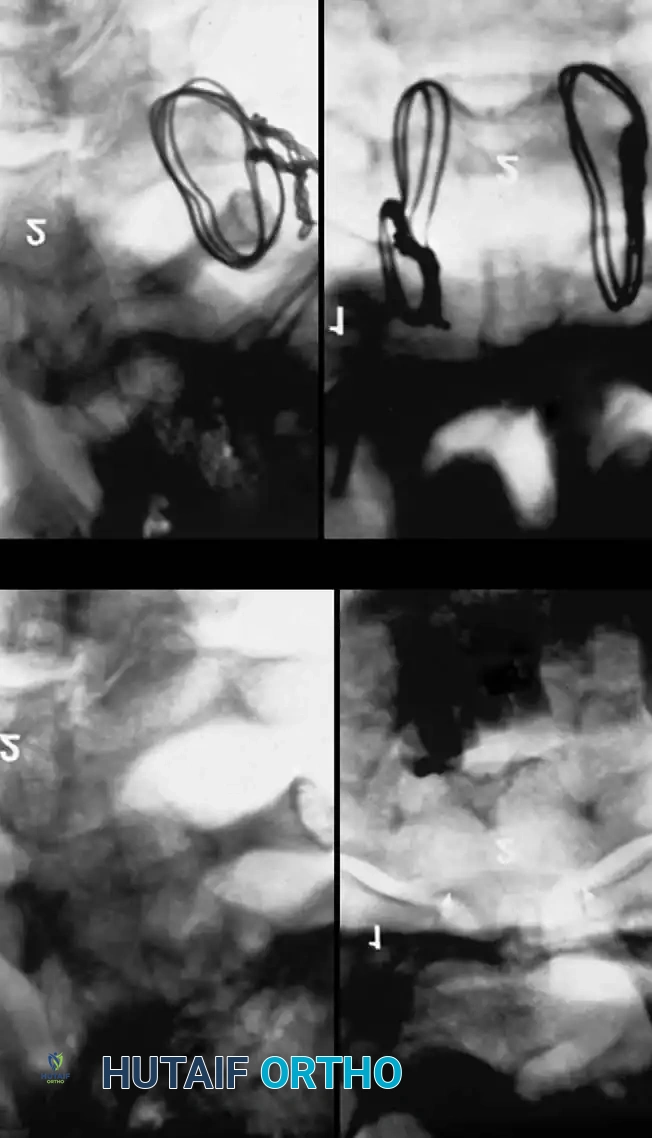

Closed Reduction via Skeletal Traction

After initial ATLS medical stabilization, spinal alignment is typically attempted via closed skeletal traction using spring-loaded Gardner-Wells tongs or a halo ring.

Traction Protocol:

* Apply an initial 10 lbs of weight to counteract the weight of the head.

* Add 5 lbs for each level of injury (e.g., a C5-C6 dislocation would require roughly 10 lbs + (5 levels × 5 lbs) = 35 lbs).

* Add weight in 5-lb increments with continuous clinical and radiographic monitoring.

* Maximum safe limits are generally considered to be 40 to 50 lbs, though some rigid dislocations may require more under strict fluoroscopic guidance.

Fig 5. Lateral radiograph demonstrating the application of cranial skeletal traction for the reduction of a cervical dislocation.